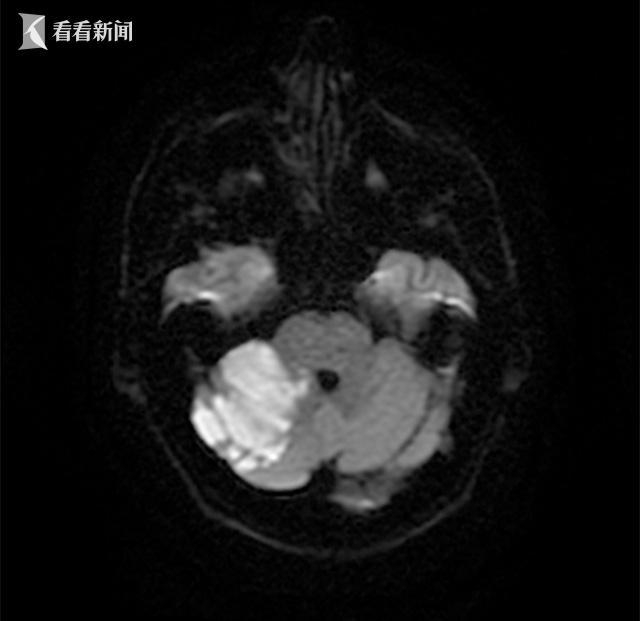

6. 脑出血

脑干、小脑、四脑室的脑出血也可表现为急性出现的眩晕发作,但往往同时伴有剧烈头痛、恶心、呕吐、肢体瘫痪、血压增高,常常很快就会进展意识不清、昏迷。导致脑出血最常见的原因是没有得到有效控制的高血压、脑动脉瘤、脑动静脉畸形等。

头颅影像学的检查(包括头颅CT与磁共振)是十分必要和紧迫的,因为我们需要快速排查急性眩晕是否是由于脑梗死或脑出血这种可危及生命的疾病引起。头颅CT可快速发现是否存在脑出血,但对发病时间很短(

脑干、小脑或四脑室的出血病情十分危重,需要进行外科手术清除血肿。即便如此,此类疾病也常常预后不佳,最终演变成持续植物状态或脑死亡也不少见。